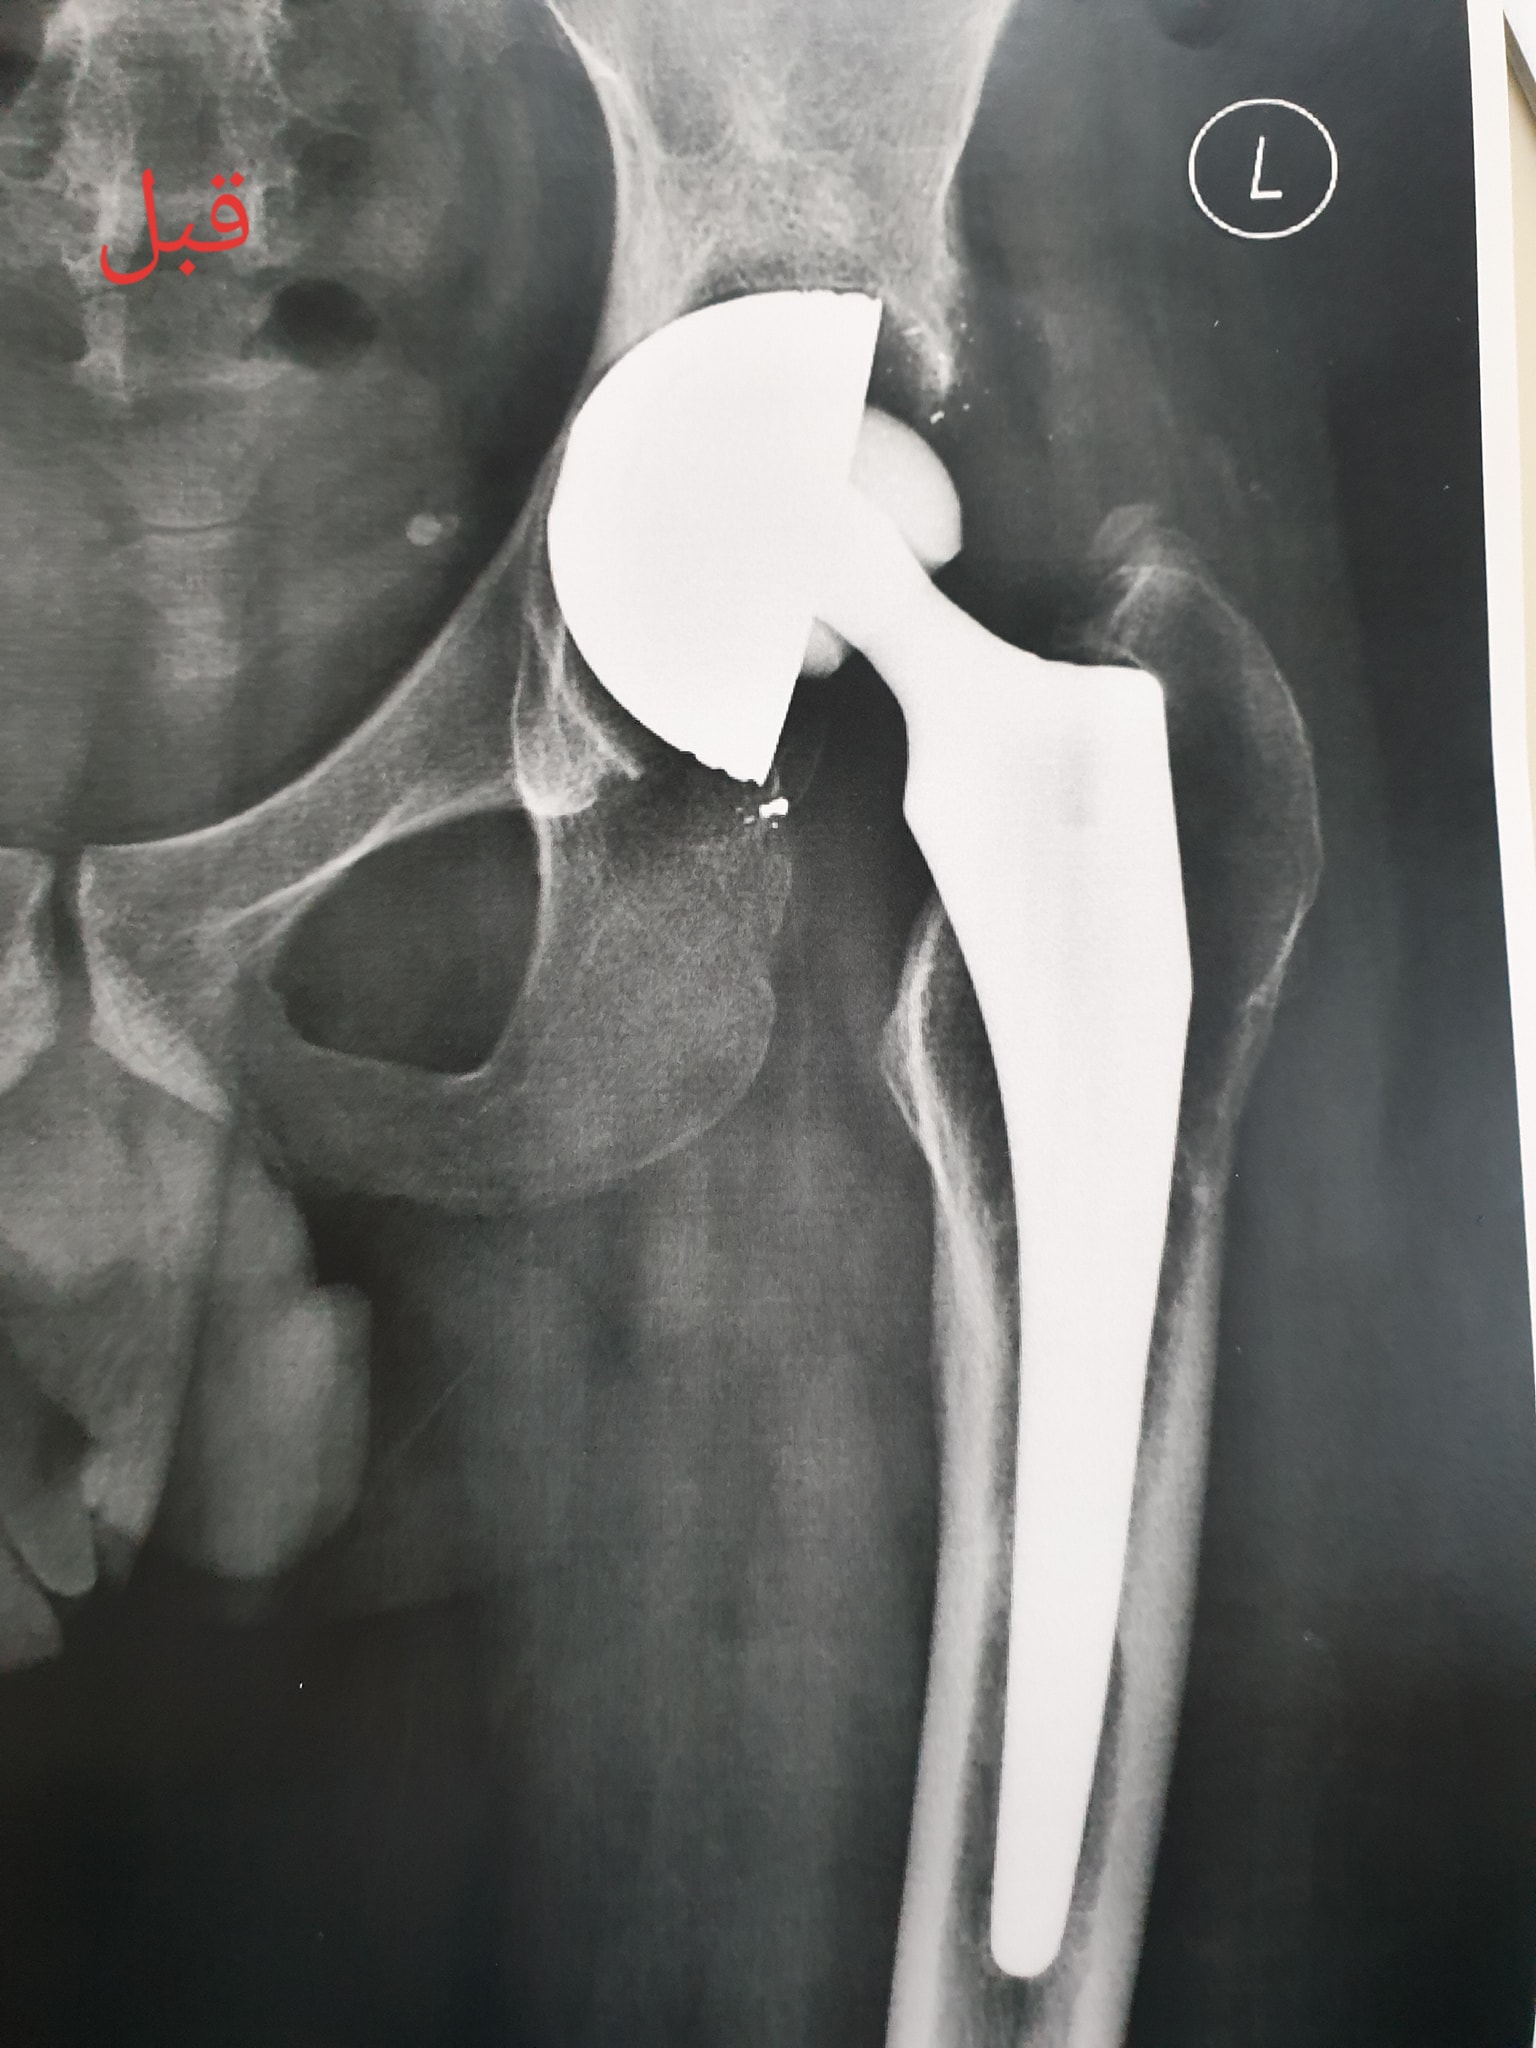

زراعة المفاصل الصناعية ورك و